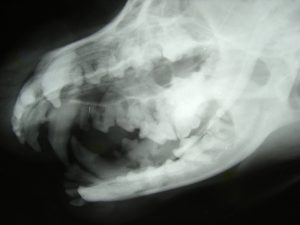

Radiology is a technique and diagnostic tool that we use to look inside the body in a completely non-invasive way and the use of digital dental radiology is a powerful tool for veterinarians who provide pets with dental care.

In other words, the use of digital dental radiology gives us a view of the internal workings of your pets’ oral cavity that we otherwise could not see with the naked eye. It’s an important diagnostic tool that helps veterinarians detect and prevent dental problems.